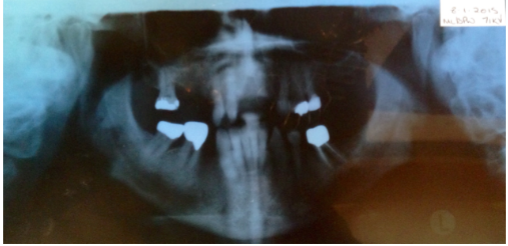

5) Maxillary CT scan confirms that there is 3.5mm (maximally) of ridge present UL anterior region